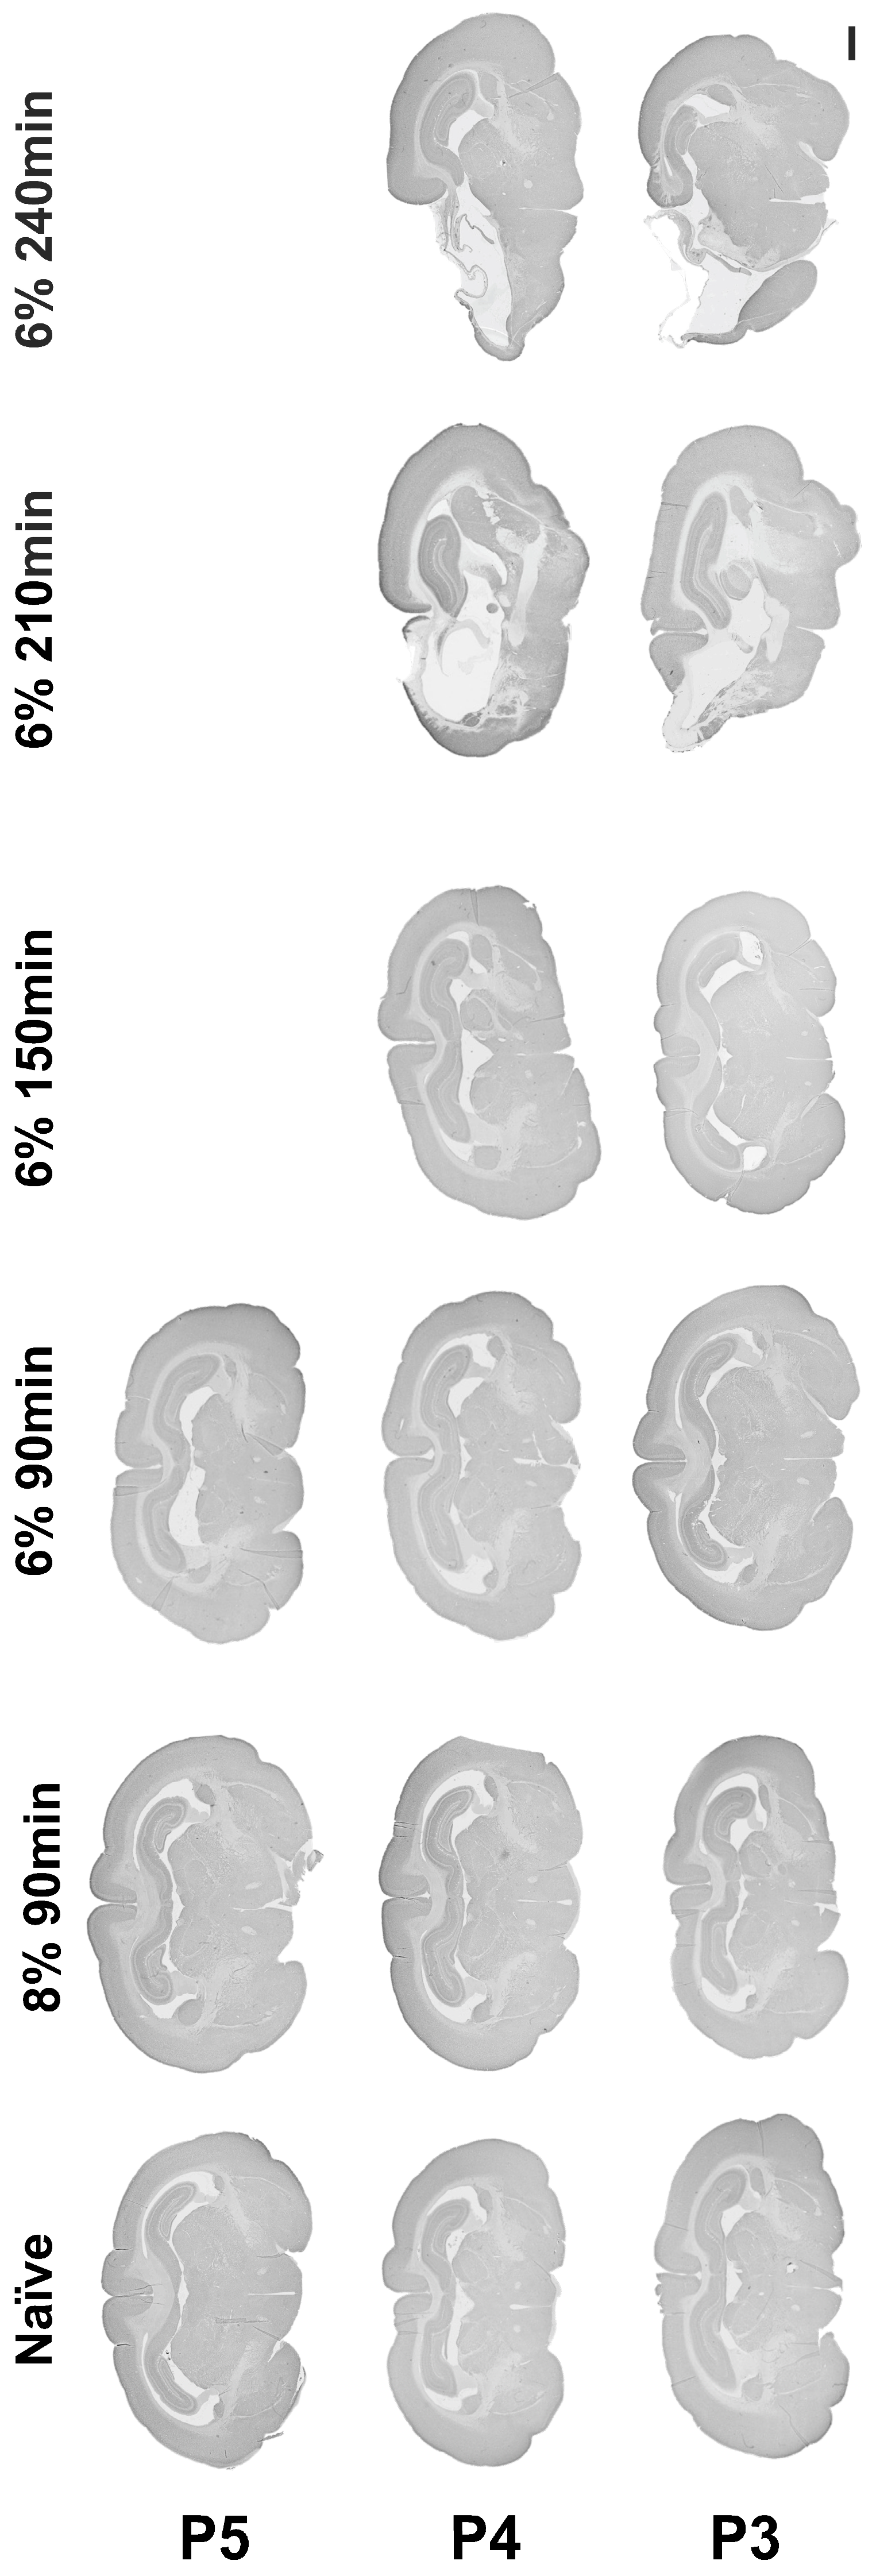

3.1. Hypoxia-Ischemia Titration